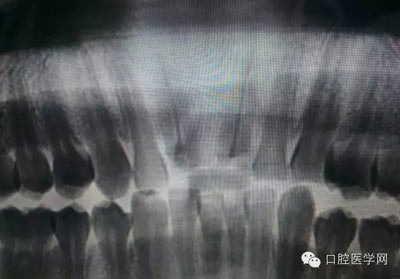

根管再治療是我們比較頭疼的,尤其是那些冠修復過的,我們有很多的麻煩需要去溝通,比如可能導致的側穿、可能沒有看到的腐質、可能導致的崩瓷,或者是后期可能出現(xiàn)冠折......這些需要我們和患者好好的溝通。全瓷冠還好些,金屬冠根測的時候很是麻煩,總之我們做修復的時候不要單純的追求速度,追求效益,適當?shù)淖⒁庀挛覀兊幕A治療和設計。